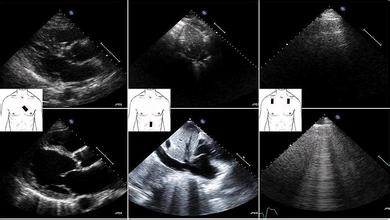

1.1 基本原则 ①简单的二维超声设备均适合肺部检查;②肺脏是气与水的紧密结合体,几乎所有病变都伴随气与水的相互消长;③大多数急性肺部病变都靠近外周并累及胸膜,所有超声征象都起自胸膜线;④肺超声征象多是基于对伪影的分析;⑤从出生到死亡肺脏一直不停地随呼吸运动,肺超声多为动态征象。

1.2 仪器要求及检查要点 目前临床使用的超声设备分辨率均适合于肺和胸膜的检查。常用实时的 B 型和时间一运动的 M 型两种超声模式。B 型由线阵换能器扫描一个解剖平面并显示二维图像,M 型记录朝探头方向来回运动的结构图像。如放置心电图 6 个电极位置那样严格限定检查时探头放置位置,可增加结果判读的可重复性和缩短检查时间。探头频率选择决定于病变位置的深度和患者的体质量指数。高频线性探头(7.5~10 MHz)适合检查表浅的胸膜及胸膜下病变,低频凸性探头(2~5 MHz)能提供很好的分辨率,适合较深部的病变和体型肥胖者。探头应始终垂直于胸壁,采用直接肋间隙法纵向扫描,横向扫查时探头轻微的移动会引起图像较大的变化。

1.4 肺超声正常解剖 相对于充气肺脏的脏、壁层胸膜的强高回声线即为胸膜线,长度约 2.5 cm,与上 0.5 cm处相邻肋骨(约 2 cm 长高回声线,间隔 2 cm)构成蝙蝠样图像称蝙蝠征。胸膜线上 0.5~1 cm 处分别为皮下组织和肋间肌肉。

1.5 正常征象

1.5.1 A 线 B 型超声下多条与胸膜线平行的高回声伪影称为 A 线。正常胸膜下充满气体的肺组织或气胸时胸膜腔内空气阻止了超声波穿透,胸壁软组织和充气肺表面的强反射形成 A 线,其深度是皮肤和胸膜线间距离的数倍。前胸壁扫查到 A 线提示肺动脉闭塞压≤18 mm Hg,特异性为 93%,敏感性为 50%,阳性预测值为 97。

1.5.2 肺滑动征 实时 B 型图像中可见脏、壁层胸膜随呼吸运动相互滑动,这种正常运动称为肺滑动征。M 型超声肋骨下 0.5 cm 可见高回声线随呼吸朝探头方向来回运动。

1.5.3 海岸征 M 型超声胸膜线上的平行线代表相对固定不动的胸壁,其下沙粒状图像代表正常的肺实质称海岸征,为肺正常动态征象。